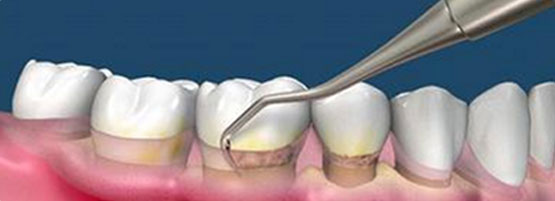

龈下洁治把龈下方的牙结石、龈下菌斑和牙周袋里的炎性肉芽组织清除,定期复诊,定期给牙周用药。是牙周病治疗中基础且有效的治疗方法。

针对症状:炎性肉芽组织、牙结石等

优势:快捷、舒适

推荐技术:龈下洁治